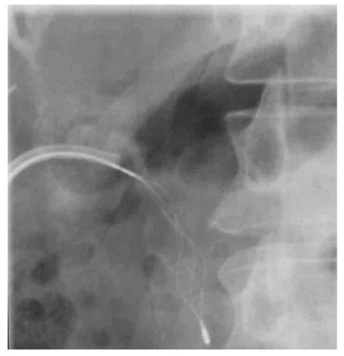

- Percutaneus trans-hepatic cholangiography (PTC) (תצלום 8.8). בשיטה זו אפשר להדגים את דרכי המרה על-ידי ניקור מלעורי של הכבד. בניקור חודרים לכלי מרה בכבד ודרכו מזריקים חומר ניגוד לדרכי המרה ה"צובע" את העץ הביליארי. שיטה זו טובה בלוקים בערכי בילירובין גבוהים, שכן בהם אין לבצע את בדיקות הניגוד.

- בשיטה זו ניתן לבצע גם ניקוז קבוע של דרכי המרה על-ידי החדרת נקז לתוך דרכי המרה (PTD - percutaneus trans-hepatic drainage). התנאי להצלחת הבדיקה הוא דרכי מרה מורחבות, שאפשר לזהות בבדיקת אולטרה-סאונד של דרכי המרה (תמונה 9.8).

- בגישה זו אפשר גם לנקז את כיס המרה בחולים עם חסימות בצינור כיס המרה (איור 4.8) או לשלוף אבנים בעזרת מכשיר מיוחד ללכידת אבנים (Basket) (תצלום 10.8).